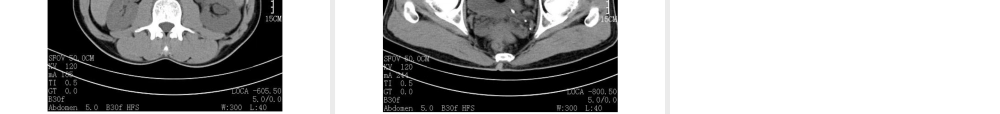

教学查房--尿石症输尿管结石温州医学院附属黄岩医院泌尿外科殷国林副主任医师基本内容介绍查房目的和内容汇报病史,重点查体病例讨论患者主诉和现病史既往史,家族史和个人史主要阳性查体主要辅助检查病例特点,诊断和鉴别诊断复习尿石症输尿管结石相关知识临床表现,病因和发病机制,诊断手段,治疗方法思考题病例介绍患者主诉和现病史既往史,家族史和个人史主要阳性查体主要辅助检查总结病例特点诊断尿石症概述肾结石、输尿管结石、膀胱结石、尿道结石总称形成机制未完全阐明,异质成核、过饱和结晶是基本学说治疗方法有了迅速发展尿结石形成环境因素气温高活动少饮水少尿液因素尿量减少,盐类有机物质浓度增加形成尿结石物质排出增加尿中抑制晶体形成和聚集的物质减少尿PH值改变尿路感染时尿基质增加泌尿系统异常病因狭窄梗阻憩室异物病理生理三个生理狭窄损伤、梗阻、积水、感染、恶性变部位、大小、数目、梗阻时间请问:输尿管结石的常见临床表现?临床表现?疼痛典型肾绞痛:程度、部位、放射血尿恶心、呕吐膀胱刺激征并发症表现诊断依据?诊断依据?病史体检:肾区叩痛实验室检查:血尿影像学检查:超声、腹部平片、排泄性尿路造影、CT输尿管镜肾镜检查鉴别诊断?阑尾炎胆囊炎卵巢囊肿蒂扭转宫外孕肠道疾病输尿管肿瘤肾盂肾炎肾周围炎治疗?治疗原则及目的?解除梗阻,保护肾功能。去除病因,防止复发。治疗方式选择保守治疗、病因治疗、药物治疗:缓解肾绞痛、多饮水、多运动、控制感染、饮食调节、调节尿液PH值体外冲击波碎石腔镜手术碎石:输尿管镜、经皮肾镜开放手术取石保守治疗大量饮水:保持每天尿量﹥2000ml饮食调节:限制钙、草酸的摄入,低蛋白、高纤维素饮食,低嘌呤饮食等控制感染:敏感抗生素调节尿pH:枸橼酸钾、重碳酸钠肾绞痛的治疗:镇痛药物、解痉药物等手术治疗腔镜手术治疗1、输尿管肾镜取石或碎石术2、经皮肾镜取石或碎石术开放手术治疗1、输尿管切开取石2、肾盂切开取石3、肾窦肾盂切开取石4、肾实质切开取石5、肾部分切除术6、肾切除术出院病人指导与预防?大量饮水调节饮食高钙摄入者减少牛奶、豆制品草酸盐结石限制菠菜、农茶高尿酸患者避免动物内脏思考题双侧上尿路结石治疗原则?双输尿管?双肾?一输尿管一肾?